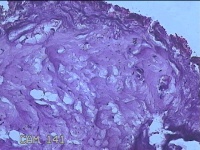

性别

女

年龄

27岁

临床诊断

乳腺脓肿

一般病史

发现右侧乳腺脓肿1个月余,伴局部疼痛不适。

标本名称

右侧乳头下方结节

大体所见

灰白暗红色结节0.8x0.5x0.3cm一个,表面糜烂。

图3

组织没固定好